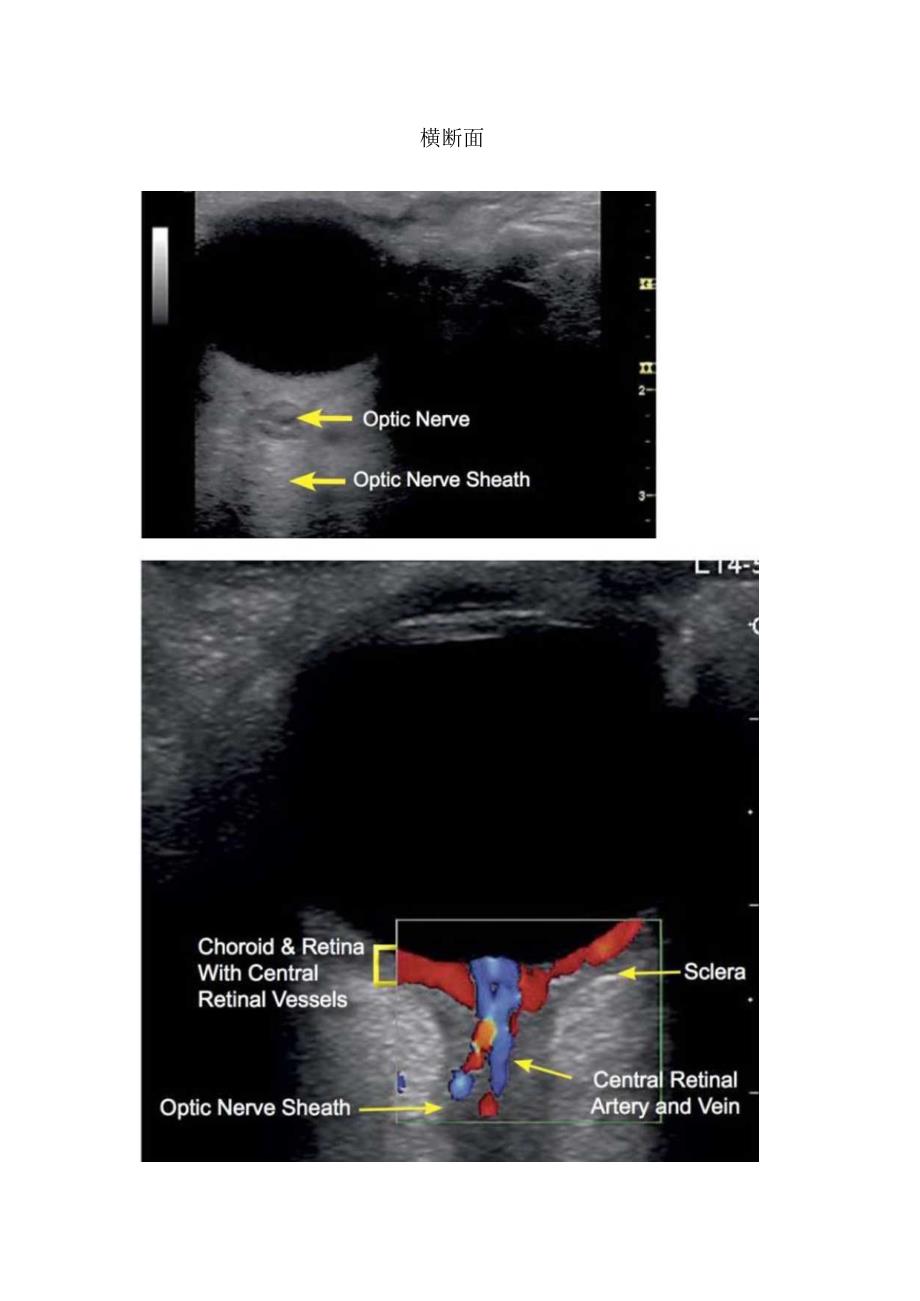

矢状切面、眼底检查等眼部超声检查结构辨认Cornea,眼角膜1.ens,晶状体Choroid/Retina,脉络膜/视网膜Opticdisk,视神经盘OpticNerve,视神经OpticNerveSheath(ONS),视神经鞘AnteriorChamber,前房矢状切面L14-SChoroid&RetinaOpticNerveSheathScleraOpticDiscOpticNerve横断面视神经检查和视网膜血管眼底检查ONDS的测量眼底检查瞳孔检查